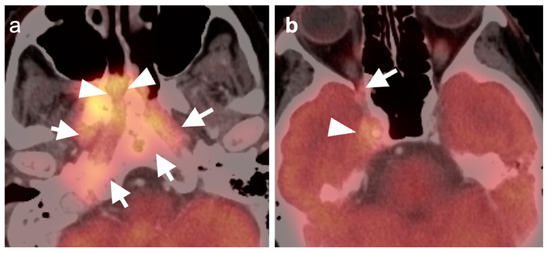

2.6. Thyroid Cancer

- Anaplastic thyroid cancer

- Bogsrud, T.V.; Karantanis, D.; Nathan, M.A.; Mullan, B.P.; Wiseman, G.A.; Kasperbauer, J.L.; Reading, C.C.; Hay, I.D.; Lowe, V.J. 18F-FDG PET in the management of patients with anaplastic thyroid carcinoma. Thyroid 2008, 18, 713–719. [Google Scholar] [CrossRef] [PubMed]